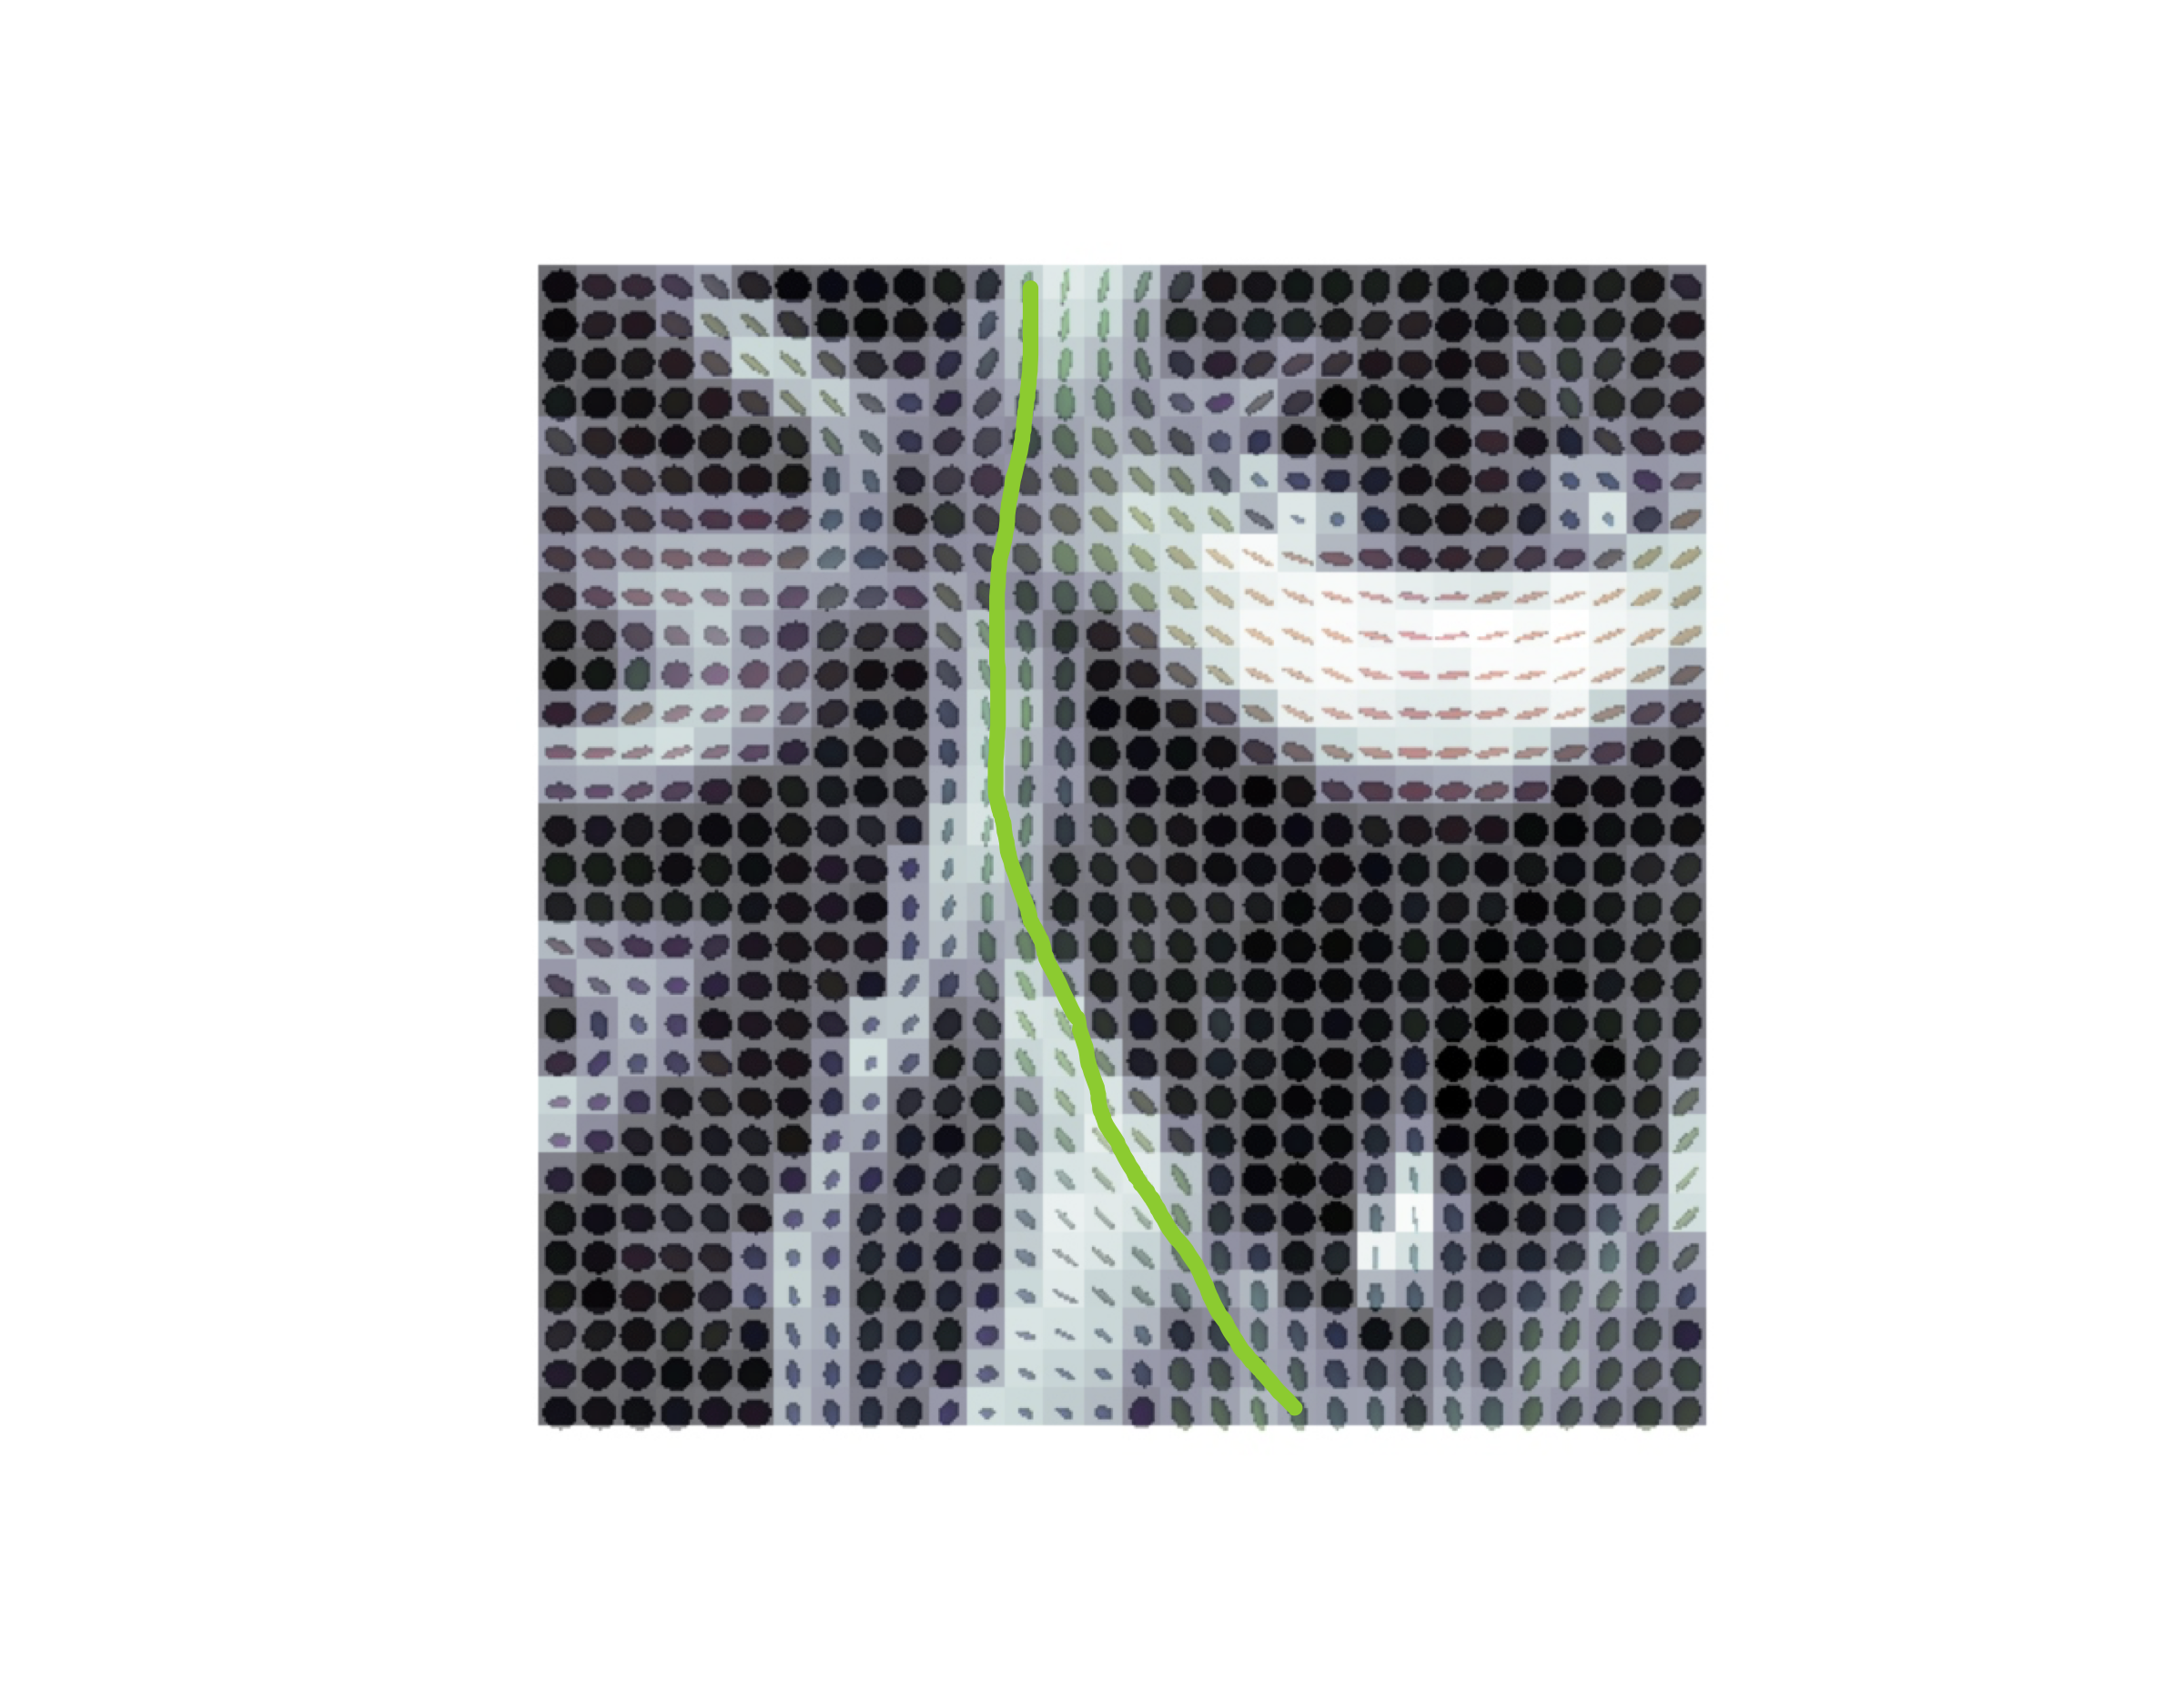

Basser (1994), Basser and Pierpaoli (1996)